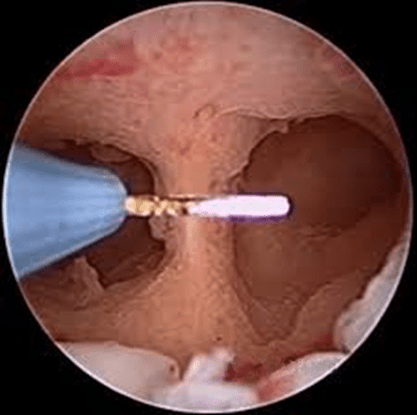

A septate uterus can be treated with a surgery called a metroplasty. The procedure is now carried out with a hysteroscopy. The hysteroscopic procedure allows for treatment to be done within the uterus without the need for an outer abdominal incision.

During a hysteroscopic metroplasty, a lighted instrument is inserted into the vagina, through the cervix and into the uterus. Another instrument is also inserted to cut away and remove the septum.

This technique is minimally invasive, and usually takes about one hour. Women choosing to have a hysteroscopic metroplasty typically return home on the same day as the procedure.